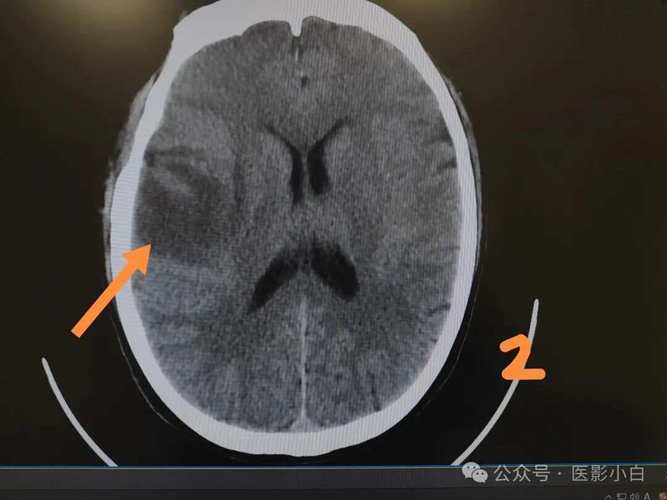

中晚期(发病6小时后,特别是24-48小时后):

- 非常清晰。 随着时间推移,缺血的脑组织开始水肿、坏死,细胞破裂,水分含量显著增加,在CT图像上,这个区域会呈现出低密度(颜色变黑)的阴影,这是CT诊断脑梗塞最典型的表现。

- 占位效应: 坏死的脑组织会引起周围水肿,可能导致脑中线移位,脑室受压变形。